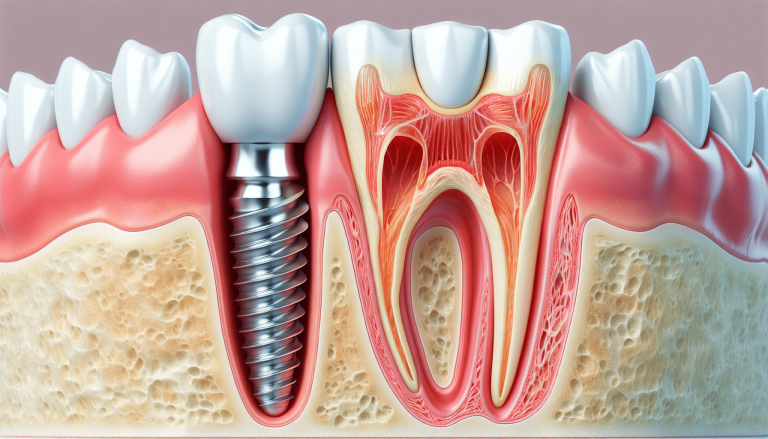

ایمپلنت دندان در کرج فرآیندی چند مرحلهای است که از مشاوره تا نصب روکش نهایی حدود ۳ تا ۹ ماه طول میکشد؛ هر مرحله سختی خاص خود را دارد اما با دندانپزشک متخصص قابل مدیریت است.

- مرحله ۳: کاشت پیچ (فیکسچر) (۱ ساعت، سختترین)

برش لثه، سوراخکاری استخوان و جایگذاری پیچ تیتانیوم با بیحسی؛ نقاهت ۱-۲ هفته با غذای نرم.

- مرحله ۴: جوشخوردگی (Osseointegration) (۳-۶ ماه، صبرطلبترین)

پیچ با استخوان جوش میخورد (فک پایین سریعتر)؛ بدون جویدن، چکاپ ماهانه؛ سختترین مرحله ایمپلنت از نظر انتظار.